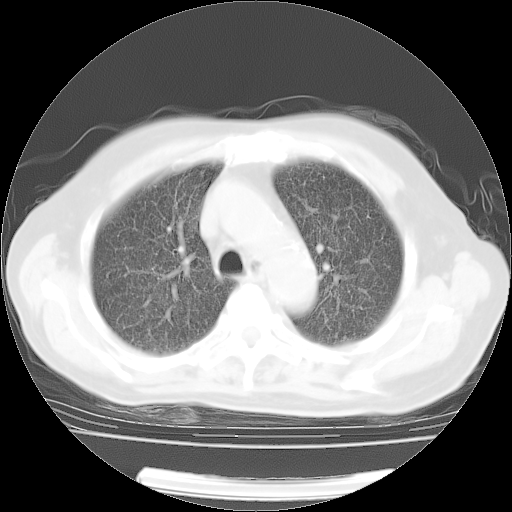

4月14日肺部CT

23.JPG

24.JPG

25.JPG

26.JPG

肺部CT平扫未见异常。